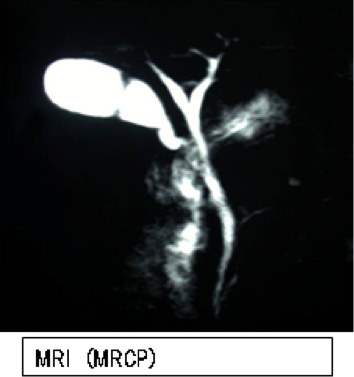

体への負担が少なく、胆石の有無や位置、胆嚢の状態を調べるための第一選択の検査です。多くの場合、この検査で診断が可能です。 - CT・MRI検査

より詳細な情報を得るために行われます。胆石の存在をさらに確認したり、総胆管や肝臓内の結石の有無、膵臓など他の臓器の状態を評価したりするのに役立ちます。